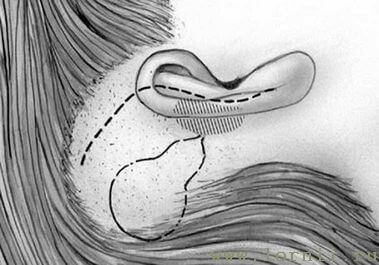

Оперативное вмешательство проводилось под ЭТН. Использовался заушный S-образный доступ (рис. 6). Формировались кожный и мышечно-надкостничный лоскуты.

Борами выполнялась антромастоидотомия (рис. 7). Через заднюю тимпанотомию вскрывалась барабанная полость (должно быть хорошо обозримо наковально - стременное сочленение, длинный отросток наковальни и окно улитки), размеры отверстия тимпаностомы должны быть не менее 3-4 мм, для нормального прохождения катушки импланта (рис. 8).

Затем борами подготавливали ложе, устанавливали и фиксировали в ложе имплант (рис. 9, 10). Соединительный кабель проводился через заднюю тимпаностому в барабанную полость.

При классической методике (у пациентов с сенсоневральной тугоухостью) катушка импланта фиксировалась на длинной ножке наковальни (рис. 11, 12).